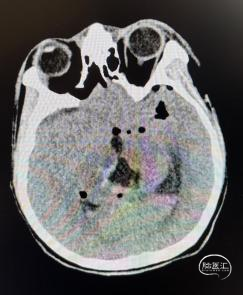

头部CT显示:松果体区见等-低-稍高密度肿块,内见少许小囊变,CT值约18-50HU,邻近脑实质受压,中脑导水管及第三脑室受压,双侧侧脑室扩大。